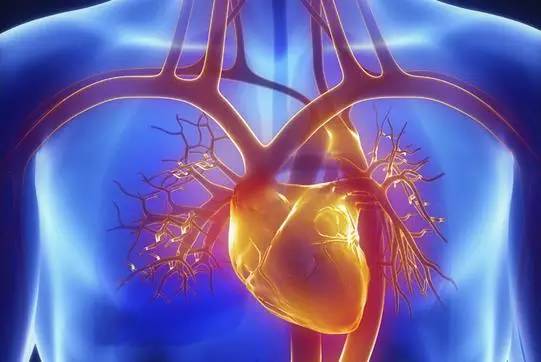

心脏——排除冠心病用CT,看心功能用超声

常规的心脏结构与功能检查,心脏彩超所提供的信息已经较为充分,又简单易行。

用CT可检查冠状动脉,但冠脉CT检查辐射量较大,不适合作为常规体检。核磁虽无电磁辐射,但对冠状动脉的观察不及CT。心脏核磁则是评价心脏结构和功能的“金标准”。